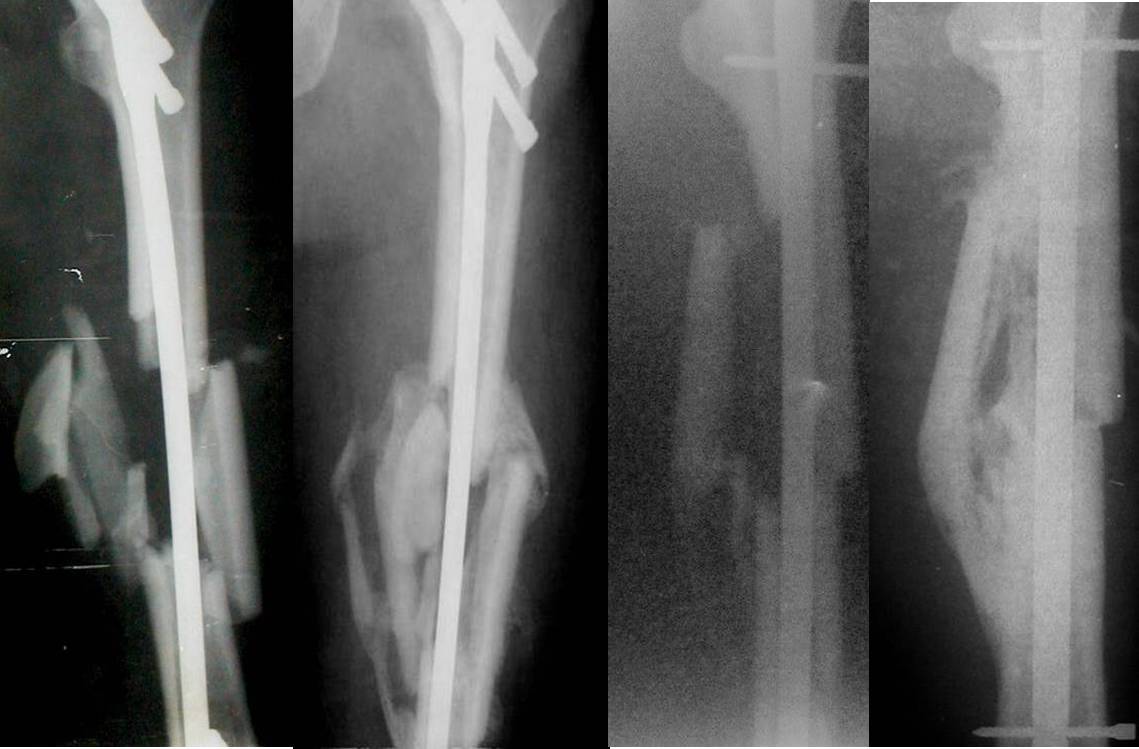

[Ortho] Бедро после БИОС осколок "лежит" далеко от отломков

Если выполнено адекватное дистальное и проксимальное блокирование и

после операции отсутствует неврологическая или сосудистая симптоматика,

нет никакой необходимости что-либо предпринимать ещё. Должно всё

срастись без всяких последствий для больного.

Примеры во вложенном файле.